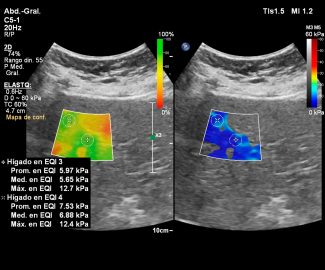

Especialista en diagnóstico por imágenes con más de 25 años de experiencia en el campo del ultrasonido y radiología digital. Trabajamos con equipos de alta tecnología garantizando la calidad y seguridad de nuestros diagnósticos, pues nuestra prioridad es la salud, bienestar y satisfacción de nuestros pacientes.

Sabemos que visitar un centro médico a veces genera nervios. Por eso, hemos creado un ambiente cálido, moderno y 100% seguro para ti. Desde nuestra cómoda sala de espera hasta nuestras áreas de ecografía, mamografía y rayos X, cada rincón está equipado con tecnología de última generación y diseñado para que te sientas en confianza.